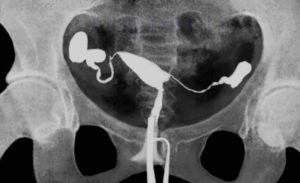

Непроходимостью фаллопиевых труб нарушает продвижения сперматозоидов к яйцеклетке. Она может быть функциональной, в данном случае никаких анатомических изменений не выявляется, но по определенным причинам нарушается функционирование маточных труб, и органической – когда в трубах происходит ряд различного рода изменений, мешающих их проходимости.

Различают частичную и полную непроходимость — гидросальпинкс. В случае частичной — непроходим лишь определенный участок трубы. В случае полной — труба непроходима полностью.